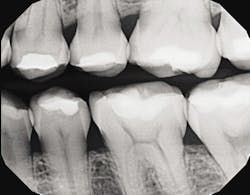

The third device, the CariVu caries detection device, uses a different type of science - near-infrared transillumination technology - to view carious lesions and cracks. Flexible "arms" on the device tip "hug" the tooth, and near-infrared photons are emitted through the arms to travel from the root to the crown of the tooth. Dense enamel reflects the photons, while porous lesions trap and absorb the photons. With the CariVu, healthy tooth appears light, and lesions appear dark. The CariVu is helpful in showing a structural view of the lesion, whether it's interproximal, occlusal, or proximal to restorations or a crack.

CariVu's diagnostic images have a high detection accuracy - an interproximal dentin caries detection rate of 99% with absolutely no ionizing radiation.1 While I take X-rays when they are necessary for a complete and effective diagnosis, CariVu helps when patients are: not due for bitewings, X-ray phobic, or reluctant to take X-rays because of a medical condition, such as radiation therapy. Because the CariVu images appear like radiographs, the patient can see the light areas of the healthy tooth and any dark, questionable, carious areas. They can see, along with me, whether I can wait to take X-rays until the next visit or whether I need to begin preventive or restorative treatment immediately. On these easy-to-read images, I can evaluate whether a carious lesion is starting or if the lesion is still in the "safe zone" (meaning it did not yet reach the dentinoenamel junction). Even if I find a questionable area on an X-ray - especially with possible interproximal decay, which can be difficult to detect, the "second opinion" of a transilluminated image can help me to determine the extent of the caries. For example, during a recent routine examination, the visual exam and radiographs did not reveal caries, but the CariVu found interproximal caries, necessitating restorative treatment.